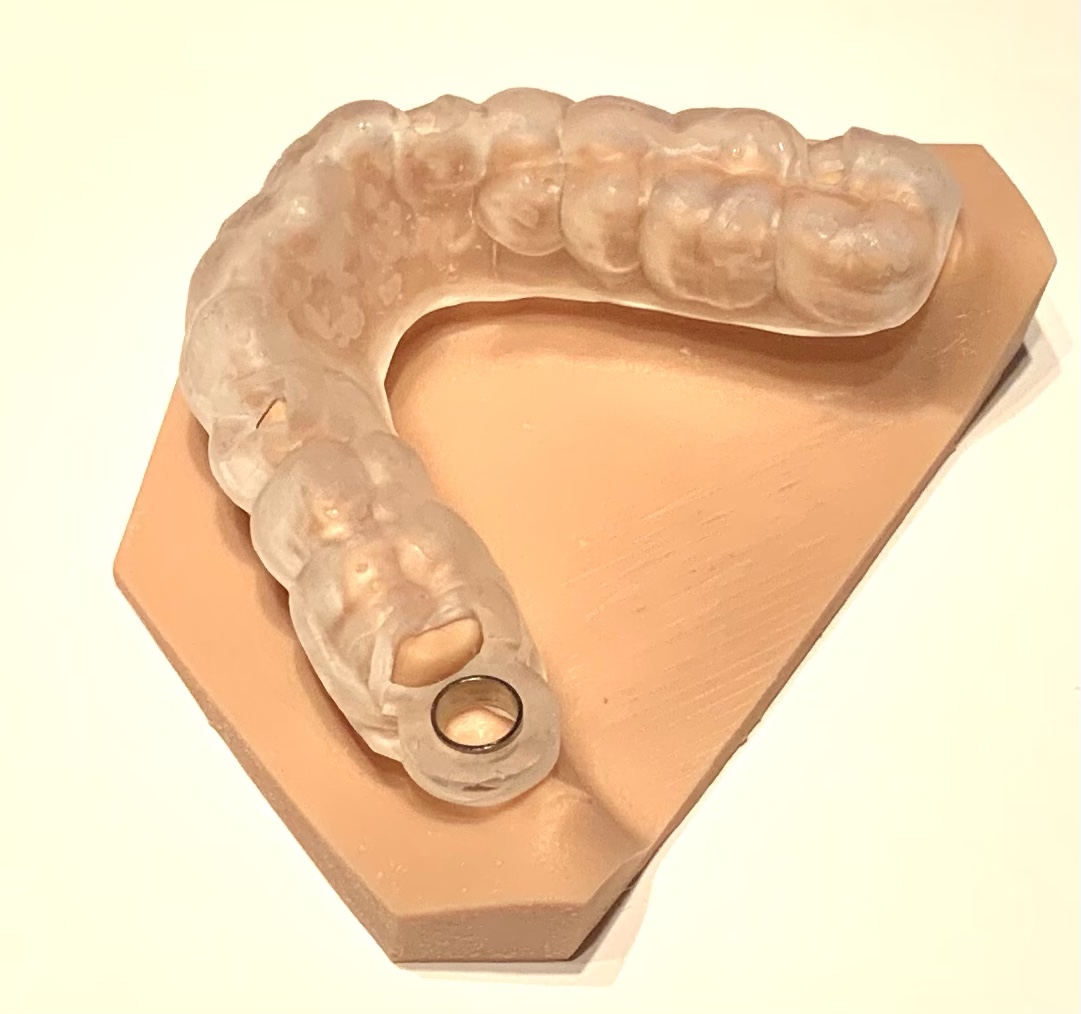

インプラントを埋入する際は、サージカルガイドを使用しました。